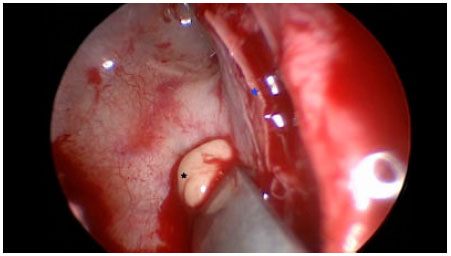

Se realizó marsupialización y descompresión, por vía endoscópica. Los puntos anatómicos referenciales estaban ausentes. En la fosa nasal derecha después de separar el septum nasal de una masa única compuesta por cornete medio, bulla etmoidal y proceso unciforme, se encontraron dos piomucoceles claramente separados en dirección antero posterior con secreción citrina y contenido purulento a la aspiración, separados por una pared ósea delgada bien delimitada (Figura 4). En la fosa nasal izquierda se identificó un piomucocele con menor cantidad de secreción purulenta. Ambas láminas papiráceas se encontraron erosionadas, con desplazamiento lateral debido a la presión externa ejercida en ambas órbitas. El reporte microbiológico del cultivo de la secreción purulenta fue informado como negativo para gérmenes comunes. El Paciente fue dado de alta al tercer día y fue controlado al décimo y trigésimo día post operatorio, donde se evidenció ausencia de epífora, sin cefalea ni obstrucción nasal, disminución de la proptosis y normalización de agudeza visual izquierda.